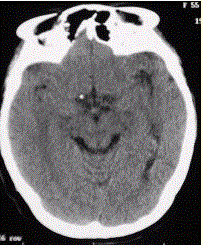

问题 患者男,20岁,癫痫病史。头部CT显示如下图。 可能的诊断是

选项 A.未见异常 B.左侧颞叶可疑低密度影 C.脑沟增宽 D.脑萎缩 E.脑结核 F.脑梗死

答案 B